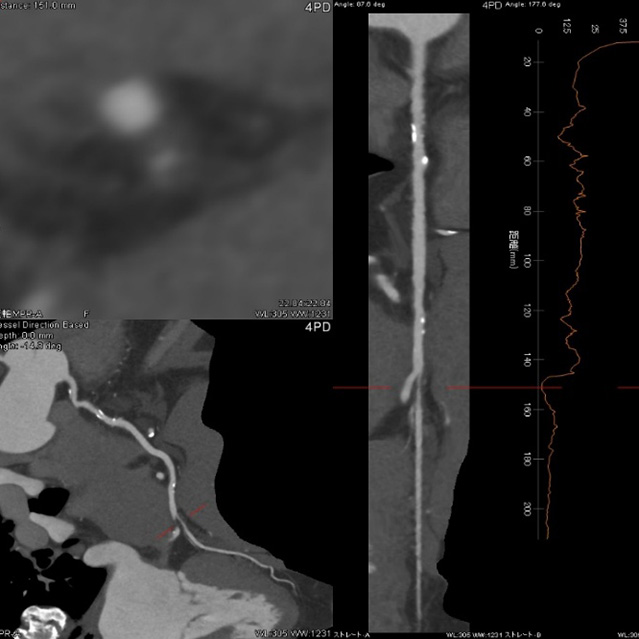

64列 MDCT Aquilion CX (canon)

80列 MDCT Aquilion PRIME (canon)

80列 MDCT Aquilion PRIME SP(canon)

大きなトンネルの中に体を入れて、X線をあてて体の輪切りの写真を撮ります。CT検査には、単純CT検査と、造影剤を注射して撮影する造影CT検査があります。